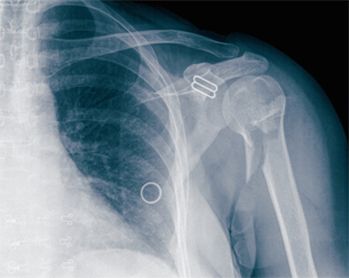

骨折:可由创伤和骨骼疾病所致,后者如骨髓炎、骨肿瘤所致骨质破坏,受轻微外力即发生的骨折,称为病理性骨折。